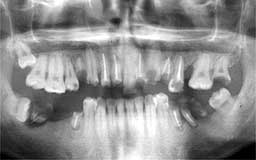

I君の初診は5歳の時で、12月30日の時間外診療で乳歯の抜髄からはじまっています。今回

の登場は親の権威で無理やり治療をしていた小学校を卒業したころからの経過です。中学校

に入るころになると子供は親の言うことを聞かなくなり、無理やり歯医者に連れて行くこと

が難しくなります。余程耐えられない痛みが生じたときだけ来院し、しかも痛みが止まれば

無断キャンセルを繰り返し最後の補綴(ほてつ)処置も行わないという誰が考えても最悪の

パターンを歩みつづけています。今回も結婚式の前にせめて前歯だけでもということで来院

されていますが、どうやらまたしても治療終了に至らないまま中断してしまいそうです。25

歳で実質喪失歯7本、すでに神経をとった歯9本、しかも咬合関係が全く狂ってしまい将来が

危ぶまれるような状況です。

| I君 当時 12歳 男性 萌出後6年も経たない第一大臼歯がすでに2本抜髄されています |

I君 13年後 25歳 抜髄して痛みが止まったら治療中止を繰り返して最悪のパターン |